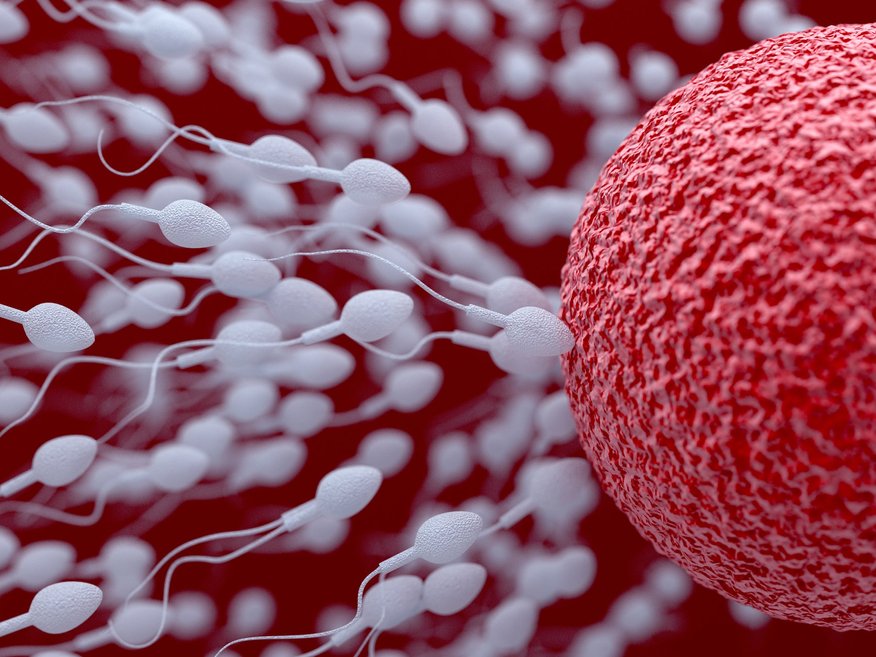

Demogrāfijas problēmas, sabiedrības dzīvesstila izmaiņas un medicīnas tehnoloģiju attīstība ir galvenie faktori, kāpēc pasaulē pieaug gan sieviešu, gan arī pāru interese par sievietes olšūnu sasaldēšanas iespējām. Sabiedrības procesu pētnieki to saista ar trīs tendencēm – atliktā grūtniecība, pāra otrreizējā neauglība un smaga saslimšana, piemēram, ļaundabīgie audzēji, kuru sekas ietekmē sievietes, vīrieša un pāra dzīves kvalitāti. Tomēr Latvijā par olšūnu sasaldēšanu vēl pastāv daudzi mīti, atzīmē speciāliste.

Kas jādara, ja plāno sasaldēt olšūnas?